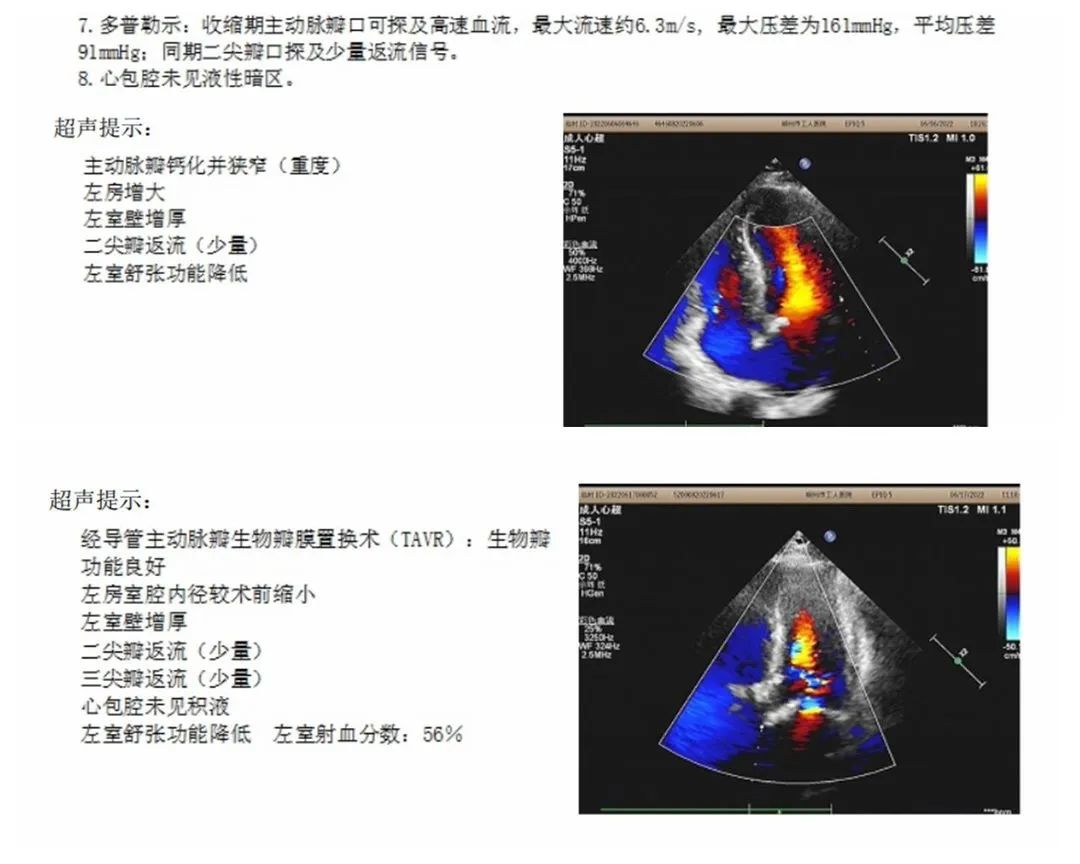

术前(上)术后(下)患者心脏彩超对比